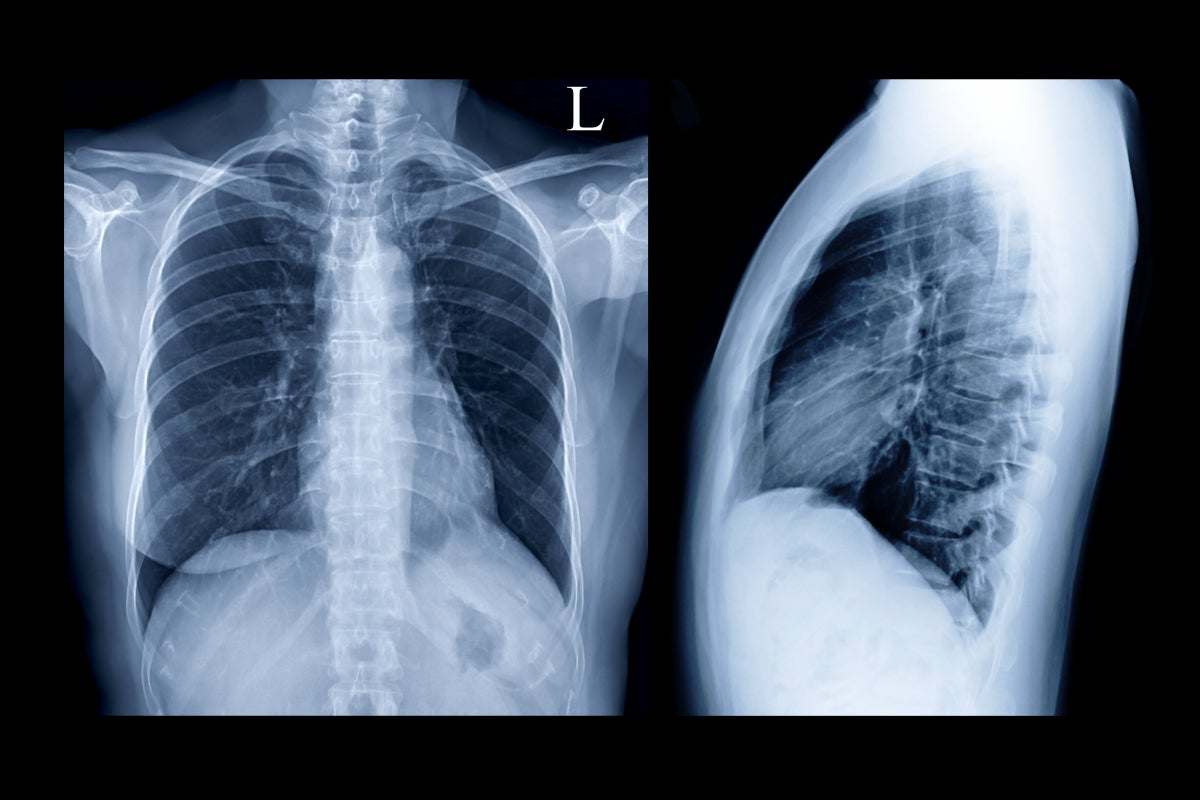

例えばレントゲンは両手で持つ必要があるくらいのサイズ(約35cmx43cm)です。

折れてしまうといけませんから、大きな風呂敷に包んで持ち運んでいました。重さも10枚なら約0.5kg、20枚なら約1kg近くにもなります。これを通院の度に持って行かなければなりません。もちろん通院の時には息子を連れ、また他にも持っていく物がたくさんありますから、もはやちょっとした重労働です。